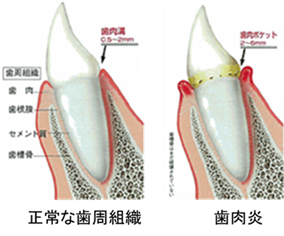

左の図は健康な歯周組織(歯肉、歯根膜、セメント質、歯槽骨)と、歯肉炎の状態を表しています。歯肉炎は炎症が歯と歯茎(歯肉)に限局して生じる病気で、歯と歯茎の境目が赤く腫れたり、出血したりします。プラークによる歯肉炎とその他薬物、ホルモンやストレスなどによるプラーク以外の歯肉炎もあります。この段階では、歯と歯茎の周りのプラークを歯ブラシなどで一生懸命除去すれば、健康な状態に戻すことは可能です。

歯茎の腫れや出血だけでなく、歯と歯茎の隙間に沿ってプラークが侵入し歯周ポケットというものを形成し、プラークがさらに根尖の方へと移動していきます。すると歯を支えている歯根膜線維が破壊され、歯槽骨が溶けて歯の動揺(グラグラする)がみられてきます。場合によっては、急性症状で歯茎に痛みがでたり、慢性的には腫れ、出血、排膿、口臭などがみられてきますが、一般的に慢性歯周炎という病名で軽度・中等度・重度に分けられています。